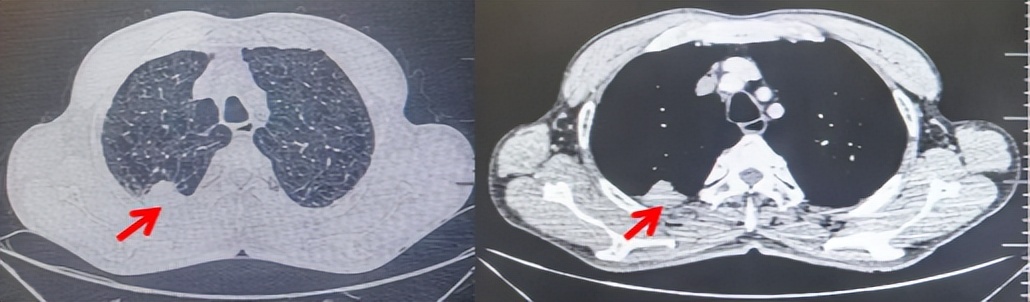

2024.09.12复查胸部CT示左侧胸膜结节,大者约为27mmx13mm,考虑转移可能性大,纵隔淋巴结增大,恶性?(如图6)。患者行胸膜穿刺活检取病理,结果示(胸膜)结合免疫组化,支持鳞状细胞癌,PD-L1(克隆号28-8)TPS约20%。分期为rT0N2bM1a IVA期,DFS为10个月。2024.09.24起行替雷利珠单抗联合紫杉醇+卡铂方案治疗4周期,复查胸CT评效SD(如图7)。后患者因脑梗塞停止治疗,于综合医院就诊,后未返院复查及治疗。

图7:替雷利珠单抗联合白蛋白紫杉醇+卡铂治疗4周期后(2024.12)胸部CT肺窗及纵隔窗